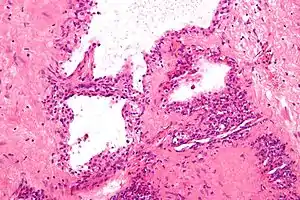

| Micrograph showing a pancreatic serous cystadenoma. H&E stain. | |